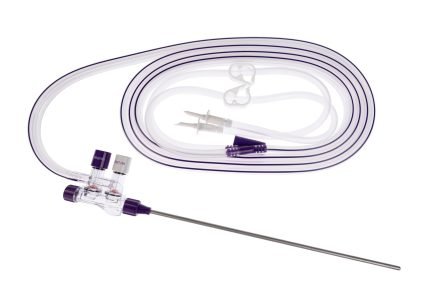

Essential Laparoscopic Suction / Irrigation System

Elite Laparoscopic Suction / Irrigation Sets